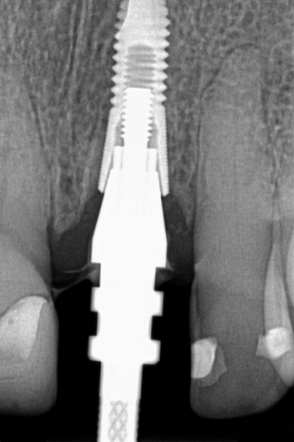

(29.) Single anterior custom abutment workflow.

Figure 29

(30.) Single anterior custom abutment workflow.

Figure 30

Individual anterior custom abutments should have straight or concave transmucosal profiles extending to the desired gingival line at the FMG (Figure 29 through Figure 35).